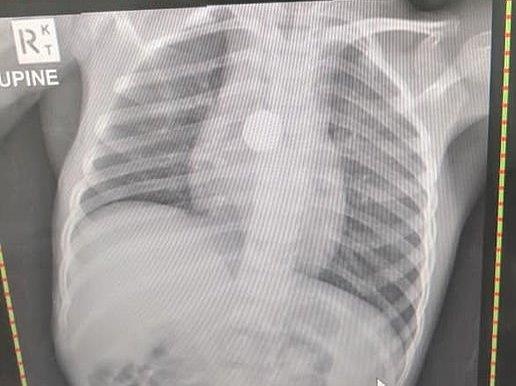

Các bác sĩ rất kinh ngạc khi chụp X-quang thấy một cục pin nhỏ bị kẹt trong cổ họng, chặn đường xuống bụng và đang ăn mòn bên trong cơ thể cô bé.

| Hình ảnh chụp X-quang cho thấy cục pin trong cơ thể của bé gái. Ảnh: Dailymail. |